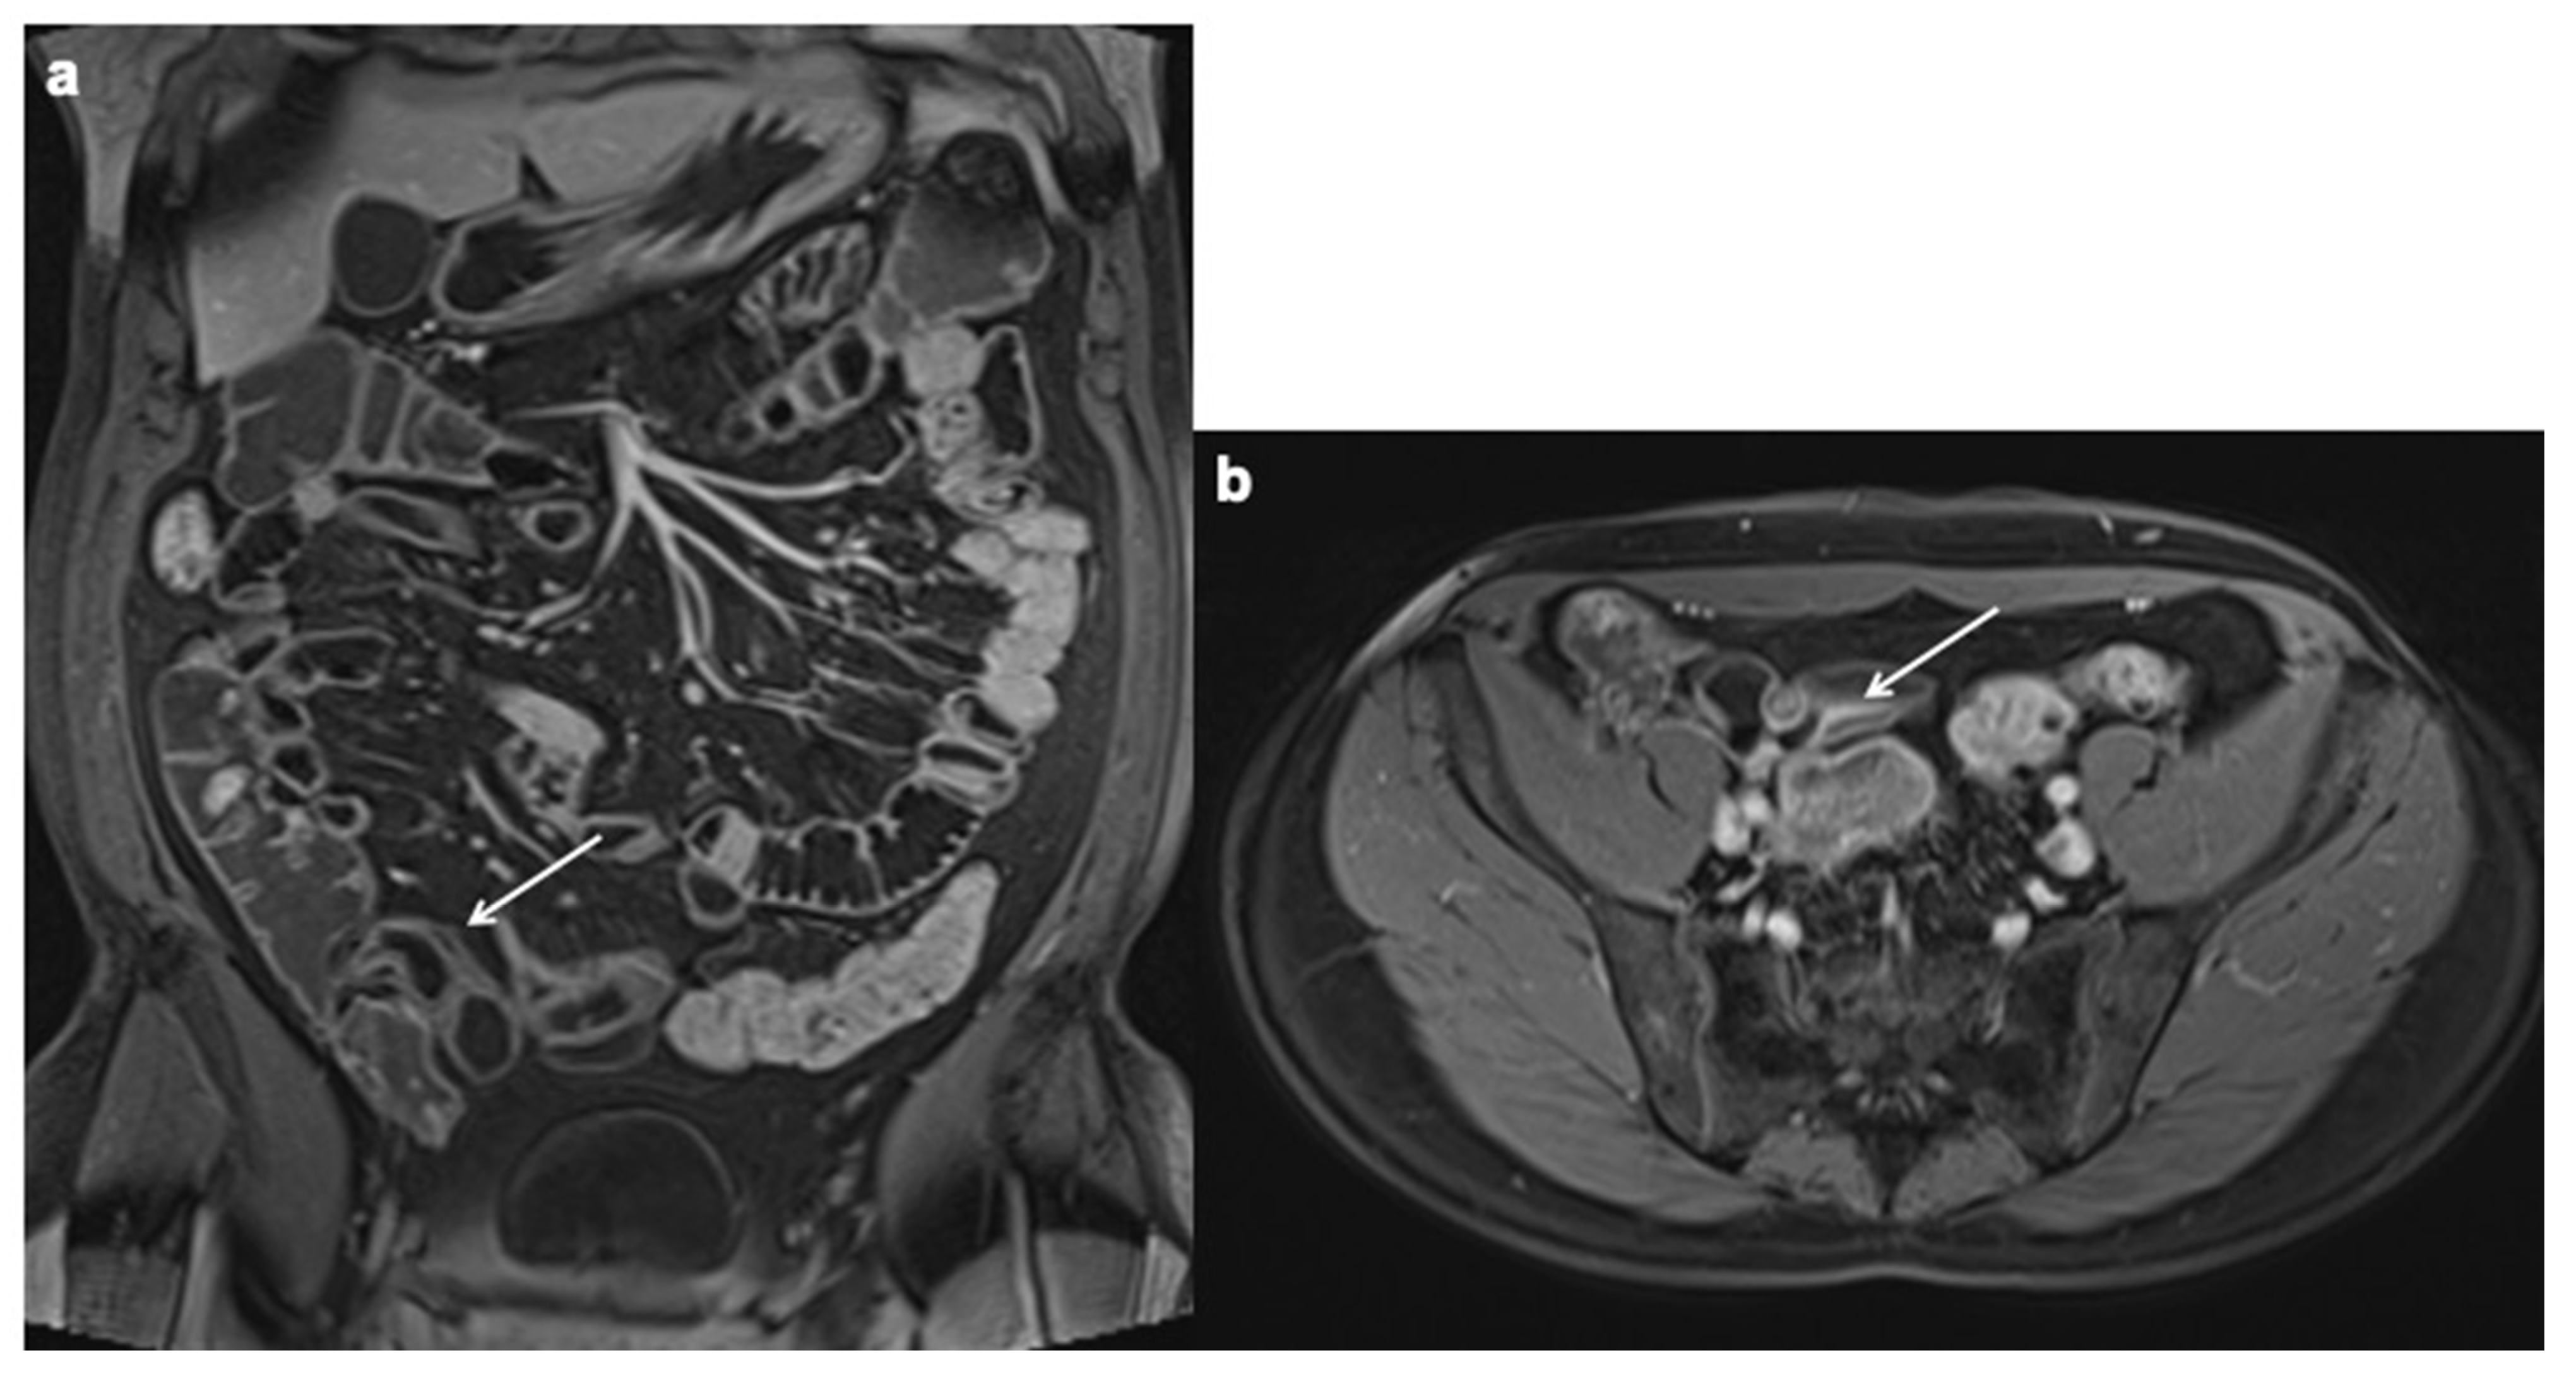

11. Imaging Findings Associated with Penetrating CD Inflammation and Complications

| Imaging findings associated with penetrating CD and complications |

| Sinus tract |

Fistula

|

| Inflammatory mass |

| Abscess |